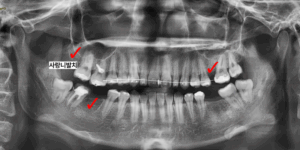

교정을 진행하여 치아들을 바르게 세운 뒤

발치를 진행했던 공간들을 적절하게 확보하여

임플란트를 식립하였습니다.

이 때, 오른쪽 아래의 맨 끝 어금니는

교정을 위해서 살려서 쓰기로 처음에는 결정했으나

교정이 끝나갈 때쯤 재평가를 통해

예후가 좋지 않아서

발치 후 임플란트로 결정을 바꾸게 되었습니다.